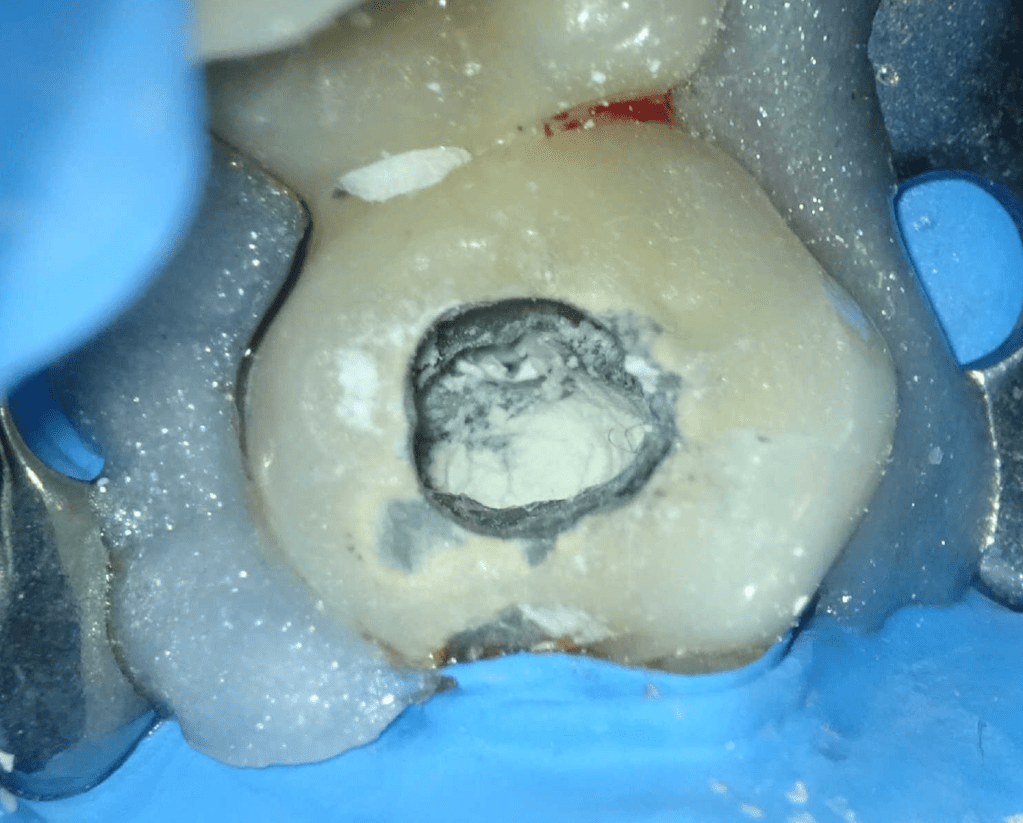

Reco pared vesticular

Reco pared vesticular